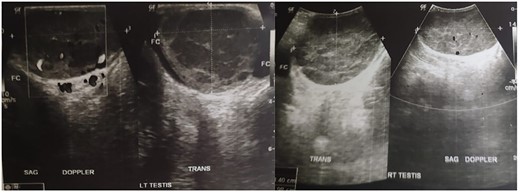

Complete blood count of the patient was unremarkable. Testicular tumour markers revealed increased in LDH (314 U/L), normal AFP (4,4 ng/mL) and normal bHCG (1,6 mIU/mL). Chest x-ray showed normal result with no lung metastasis. Ultrasonography (USG) examination revealed semi-solid spongiform mass in the right epididymis and bilateral testicles, suggestive malignancy and minimal bilateral hydroceles (Fig. 1). Bilateral radical orchiectomy under general anaesthesia was done.

PTL usually presents as unilateral [3], firm and painless testicular mass [4], and this could be why the patient in this case neglected his condition. Bilateral synchronous involvement, as seen in this case, occurs only 6–10% of all cases [5]. USG result may show hypoechogenicity with hypervascularity in a diffuse or focal area [6].

Diagnosis is based on history taking, physical examination and USG imaging. HIV serology should better be performed as it has high concurrency with Non-Hodgkin Lymphoma [7]. In this case, testicles revealed enlarged right epididymis and bilateral testicles with minimal bilateral hydrocele, accompanied by spongiform semi-solid lesions in the right epididymis and bilateral testicles; suggestive malignancy according to USG examination. When PTL is suspected, inguinal orchiectomy is required to achieve optimal disease control and adequate pathologic specimen. IHC examination from the case indicated CD20, which strongly positive and diffuse in tumour cells [8].